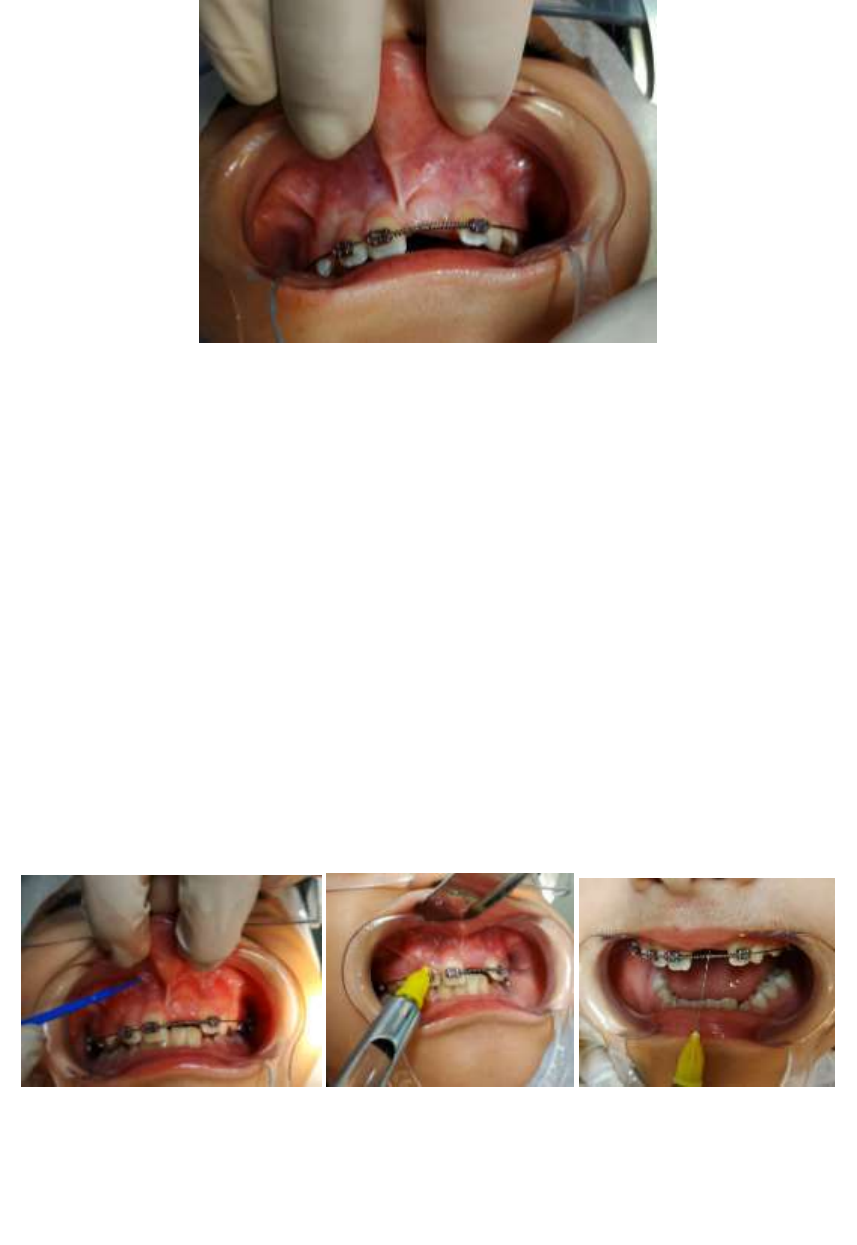

freio labialfreio superiorfreio emfreio bebefreio Freiofreio lingual:freio TUDOfreio ofreio quefreio vocêfreio precisafreio saberfreio sobrefreio ofreio assunto!freio FRENECTOMIAfreio Grátis:freio FREIOS